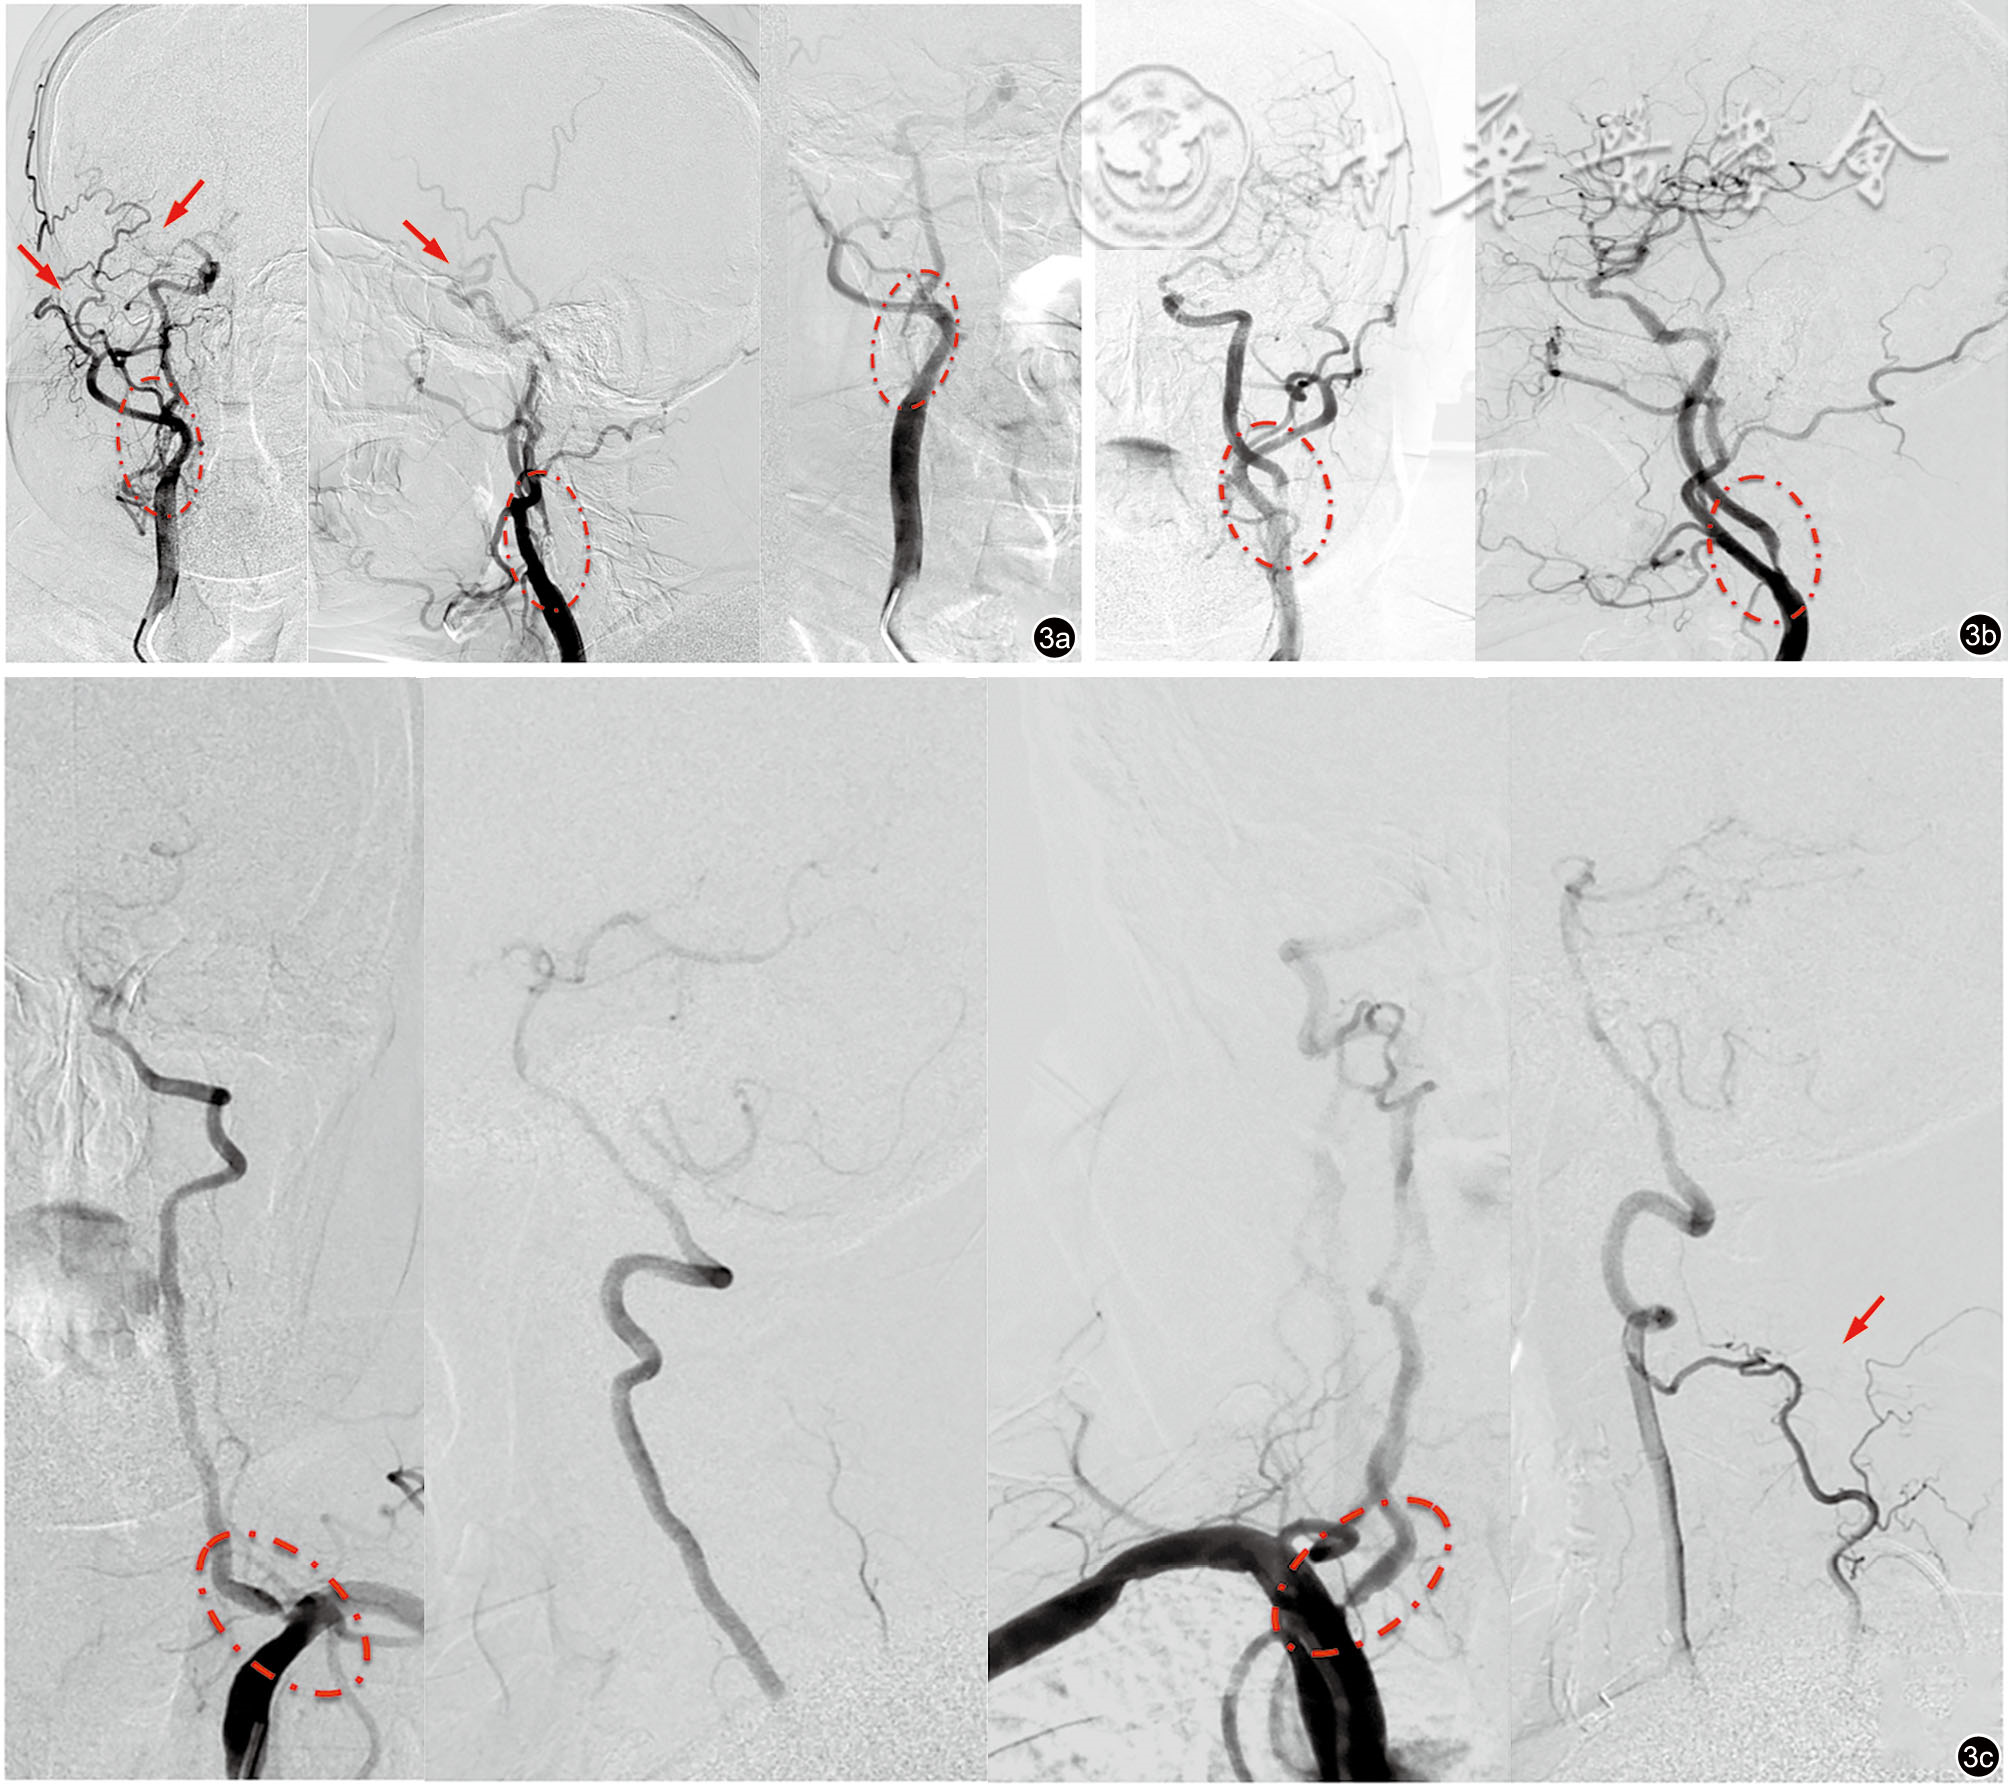

图3 术中该患者的数字减影血管造影(DSA)影像。图a为右侧颈总动脉造影,圆圈内为右侧颈内动脉起始段重度狭窄,红色头所指右侧大脑前动脉及大脑中动脉显影浅淡,前交通动脉未开放;图b为左侧颈总动脉造影,圆圈内为左侧颈内动脉起始段重度狭窄,红色头所指左侧大脑前动脉A1段闭塞:图c为双侧椎-基底动脉造影,圆圈内为双侧椎动脉起始段重度狭窄,红色头所指右侧颈升动脉经肌支代偿部分右侧椎动脉颅内血流

图4 术后患者的数字减影血管造影影像。图a为左颈总动脉造影可见支架植入顺利,残余狭窄<30%,颅内远端血流改善,但左侧大脑前动脉A1仍未显示;图b为右侧锁骨下动脉-椎动脉造影,支架植入效果满意,狭窄解除;图c为左侧锁骨下动脉-椎动脉造影,支架植入效果满意,狭窄解除 注:LCCA为大动脉粥样硬化型